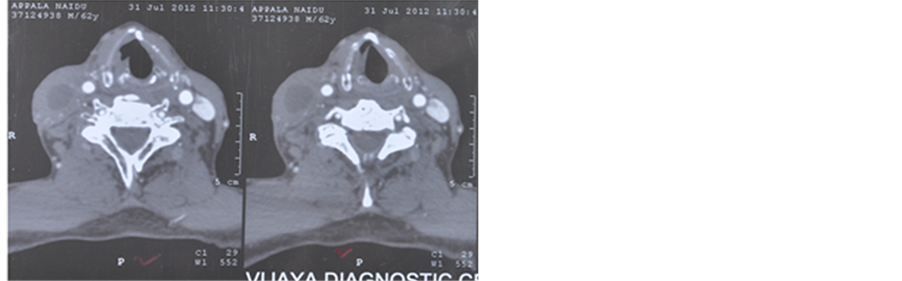

3 cm in the right upper neck level IIB. Another swelling of size 4 cm × 2 cm was present on the right side of neck in the submandibular region of level IB. Upper gastro intestinal endoscopy and CT scan revealed an ulceroproliferative irregular growth in the right posterior 1/3rd of tongue. It was extending from the right posterolateral base of the tongue and to the vallecula. Lesion was measuring 4 cm × 3 cm. Biopsy was taken from growth on posterior one third of tongue. It revealed squamous cell carcinoma grade 2. He was diagnosed to have carcinoma oropharynx T4aN2bM0.

He was started on weekly cisplatin 40 mg/m2 and nimotuzumab 200 mg for a total of 6 cycles. Radiation was delivered to a total dose of 60 Gy/30 fractions/6 weeks through parallel-opposed portals on Co-60. At first follow up, clinical examination did not revealed any lesion and CT scan showed small residual induration measuring 1 cm × 0.8 cm on the right base of the tongue which depicted considerable decrease in the size of the lesion (Figure 2). Biopsy of this lesion was negative for malignancy. Patient has been on follow-up for 6 years and is doing well with good general condition. He has reported no adverse reactions related to nimotuzumab.

Pre treatment Post 1 year after treatment

Figure 2. (a) Pretreatment―CECT of neck showing an oropharyngeal growth involving the right base of tongue; (b) Post treatment―CECT of neck showing small residual thickness in the right oropharyngeal region.

Figure 3. (a) Pre-treatment CT scan showing a mass measuring 3.6 cm × 2.5 cm × 2.0 cm on the right lateral oropharyngeal wall; (b) Post-treatment CT scan showing reduction in the size of submandibular lymph node to 0.5 × 0.5 cm.